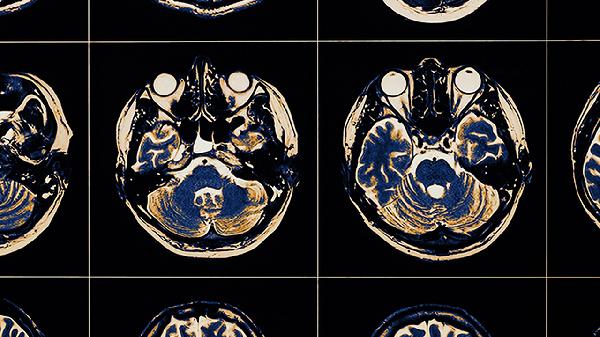

脑淤血压迫神经导致四肢不能动可以通过一般治疗、服用药物、注射药物等方式改善,当脑部受到外伤或患有高血压时,会引起脑出血,出血灶压迫神经或脑组织后,会对神经造成损伤引起四肢瘫痪的症状。